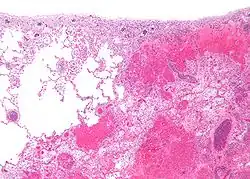

Micrografía de tejido pulmonar infartado (derecha de la imagen) junto a tejido pulmonar relativamente normal (izquierda de la imagen). Tinción H/E.

Infarto del pulmón debido a embolia pulmonar.